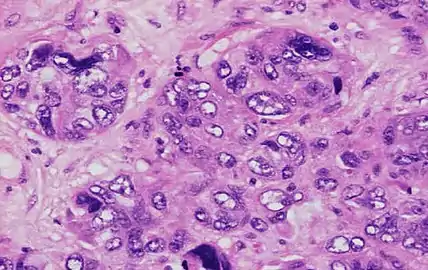

The grading of a cancer in the breast depends on the microscopic similarity of breast cancer cells to normal breast tissue, and classifies the cancer as well differentiated (low-grade), moderately differentiated (intermediate-grade), and poorly differentiated (high-grade), reflecting progressively less normal appearing cells that have a worsening prognosis. Although grading is fundamentally based on how biopsied, cultured cells behave, in practice the grading of a given cancer is derived by assessing the cellular appearance of the tumor. The closer the appearance of the cancer cells to normal cells, the slower their growth and the better the prognosis. If cells are not well differentiated, they will appear immature, will divide more rapidly, and will tend to spread. Well differentiated is given a grade of 1, moderate is grade 2, while poor or undifferentiated is given a higher grade of 3 or 4 (depending upon the scale used).

The Nottingham system[12] is recommended for breast cancer grading.[13] The Nottingham system is also called the Bloom–Richardson–Elston system (BRE),[14] or the Elston-Ellis modification[15] of the Scarff-Bloom-Richardson grading system.[16][17] It grades breast carcinomas by adding up scores for tubule formation, nuclear pleomorphism, and mitotic count, each of which is given 1 to 3 points. The scores for each of these three criteria are then added together to give an overall final score and corresponding grade. It is not applicable to medullary carcinomas which are histologically high-grade by definition, while being clinically low-grade if lymph nodes are negative.[18] It is also not applicable to metaplastic carcinomas.[19]

The grading criteria are as follows:

Tubule formation

Tubule formation score in the Nottingham system

This parameter assesses what percent of the tumor forms normal duct structures. In cancer, there is a breakdown of the mechanisms that cells use to attach to each other and communicate with each other, to form tissues such as ducts, so the tissue structures become less orderly.